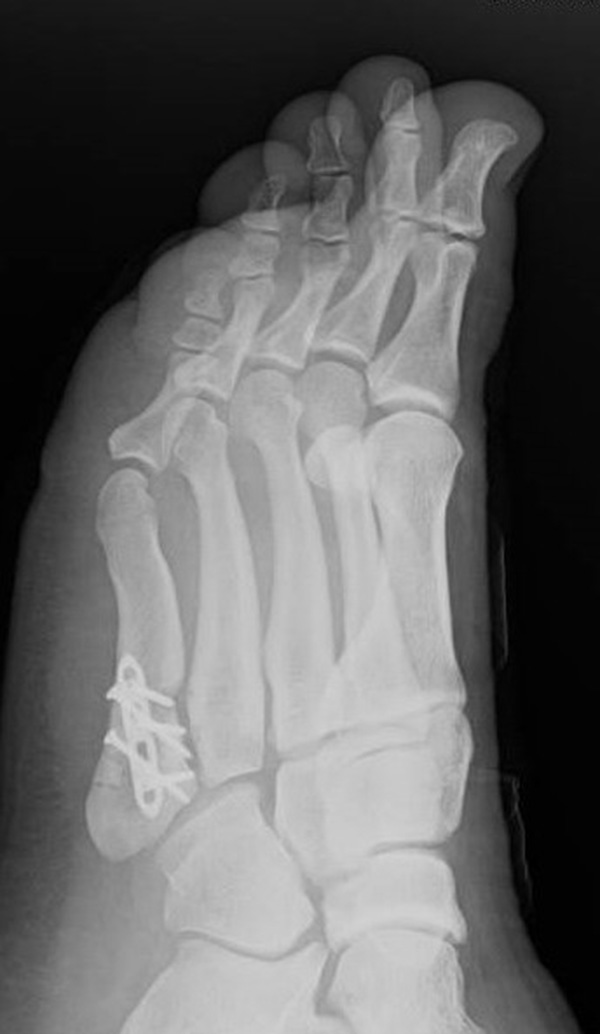

Abb. 12a: Typ III Deformität präoperativ im belasteten dp Röntgenbild.

Abb. 12b: Dorsoplantare Röntgenkontrolle nach medial schließender Osteotomie mit Schraubenosteosynthese.

Abb. 12c: Schrägaufnahme nach medial schließender Osteotomie mit Schraubenosteosynthese.

Abb. 12d: Seitliche Aufnahme nach medial schließender Osteotomie mit Schraubenosteosynthese.